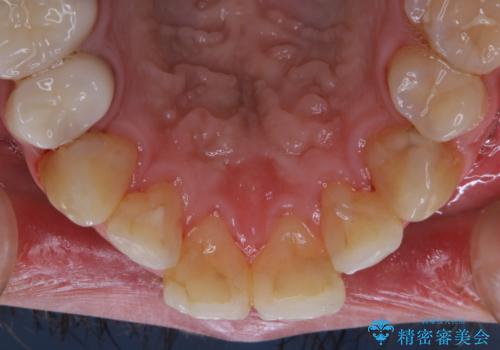

インビザライン矯正治療のスキャニング前のPMTC

- インビザラインでのスキャニング前にPMTCを希望されました。PMTC60分コースを行いました。

矯正治療前には、PMTCで歯石や汚れを取り除き、健康的な歯肉の状態にすることが大切です。PMTCでは、がたつきになどより、ご自身では取り切ることのできない細かい部分などに付着した汚れなども、専門的な機械や材料を使用してクリーニングを行います。

また、しっかりと汚れを除去することで、虫歯や歯周病などを早期発見することができます。